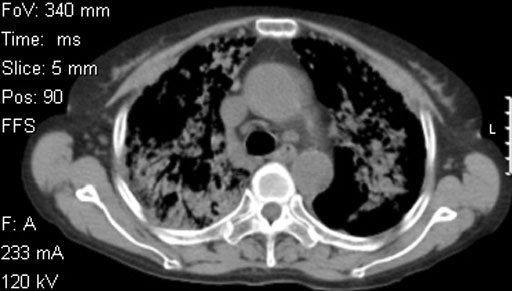

• 図3c 胸部単純CT

(肺条件)

• 図3d 胸部単純CT